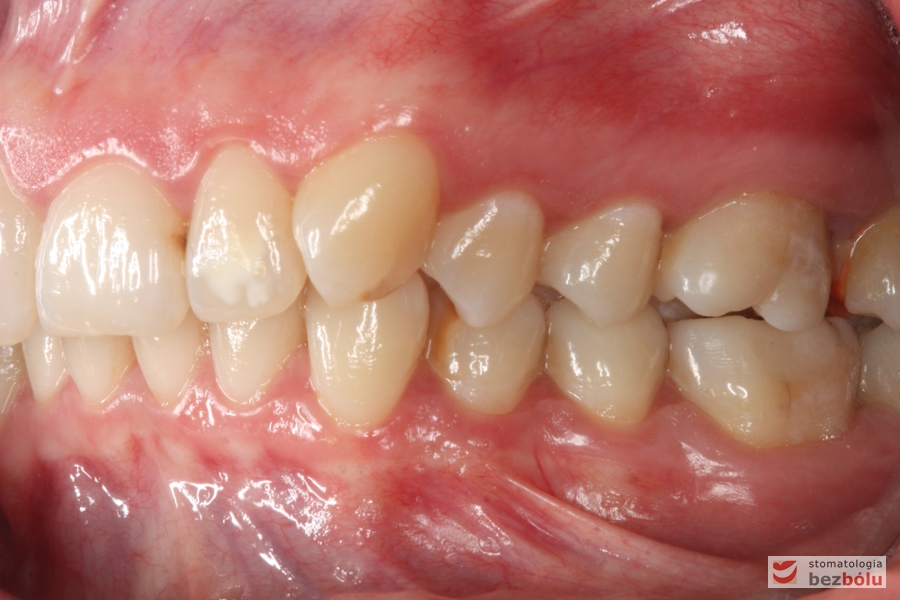

Pacjentka lat 26 zgłosiła się do gabinetu celem korekcji uśmiechu. Głównym zmartwieniem były problemy estetyczne, które znacznie wpływały na jakość życia pacjentki. Wykonano leczenie zachowawcze zębów oraz analizę cefalometryczną i analizę modeli diagnostycznych. Zaplanowano leczenie aktywne aparatem DAMON dla szczęki i żuchwy, które trwało 2 lata. Po fazie leczenia aktywnego rozpoczęto leczenie retencyjne z użyciem szyny tłoczonej dla szczęki i retainera stałego dla żuchwy.